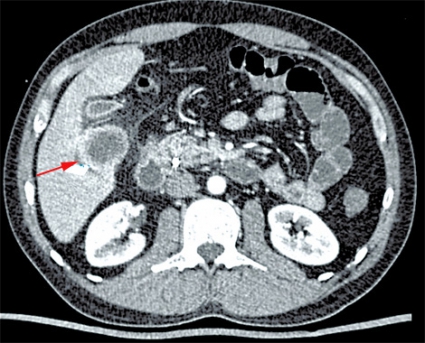

Fall 2. En 34-årig man från Tunisien sökte vård för buksmärta och hög feber. Patienten var ikterisk och visade tecken till gallstas. Antibiotikabehandling inleddes då den kliniska bilden talade för kolangit. Utredning med ultraljud och DT påvisade två cystiska förändringar i levern (5 respektive 6 cm stora), båda såg ut som ekinokockcystor. Blodprov visade stegrat CRP och eosinofili. Serologisk diagnostik bekräftade diagnosen. Gallvägarna avlastades med stentning via endoskopisk retrograd kolangiopankreatografi (ERCP) på grund av en intrahepatisk striktur (Figur 2). Behandlingen förbättrade initialt kolangiten, men patienten fick flera recidiv.

Radiologisk utredning av ekinokockcystor har flera målsättningar. Den ska bidra till diagnostiken och till en anatomisk kartläggning av utbredning och eventuella komplikationer, bedöma cystans viabilitet och underlätta preoperativ planering. Den radiologiska diagnostiken av ekinokockcystor i levern har centrerats runt ultraljud men har på senare tid ofta ersatts med DT och MR. Radiologiska fynd som talar för ekinokockcysta utgörs framför allt av cystvägg med dubbelkontur, multivesikulärt utseende och väggförkalkningar (talar för inaktiv cysta). Viktigt att komma ihåg är att kalcifiering av väggen förekommer inte bara vid inaktiva (CE4 och CE5) cystor utan även i upp till 50 procent vid alla stadier [7]. WHO-klassifikationen av ekinokockcystor grundas på ultraljudsundersökning men kan överföras till antingen DT eller MR [2, 3]. Cystans relation till gallvägar, kärl och extrahepatisk vävnad bedöms enklast med DT eller MR. Om fistulering till gallvägar misstänks kan MR med kolangiopankreatikografisekvenser och i vissa fall endoskopisk retrograd kolangiopankreatikografi (ERCP) bidra till noggrann anatomisk kartläggning inför planerad resektion [8].